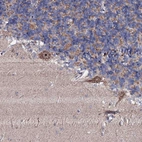

Immunohistochemical staining of human cerebellum shows strong nucleolar positivity in purkinje cells.